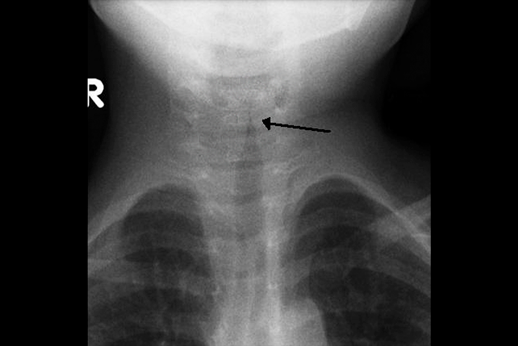

Radiografia cervical: Pode demonstrar típico estreitamento subglótico do crupe em incidência posteroanterior (sinal da ponta de lápis ou torre de igreja). Desvantagens: Esse sinal pode estar presente em pacientes saudáveis e, se presente na vigência do quadro agudo, não se correlaciona com gravidade da doença. A radiografia é útil quando há suspeita de aspiração de corpo estranho, ou seja, para diagnóstico diferencial.

Texto alternativo para a imagem Figura 3. Sinal da torre de igreja. Créditos: Frank Gaillard/Wikimedia commons